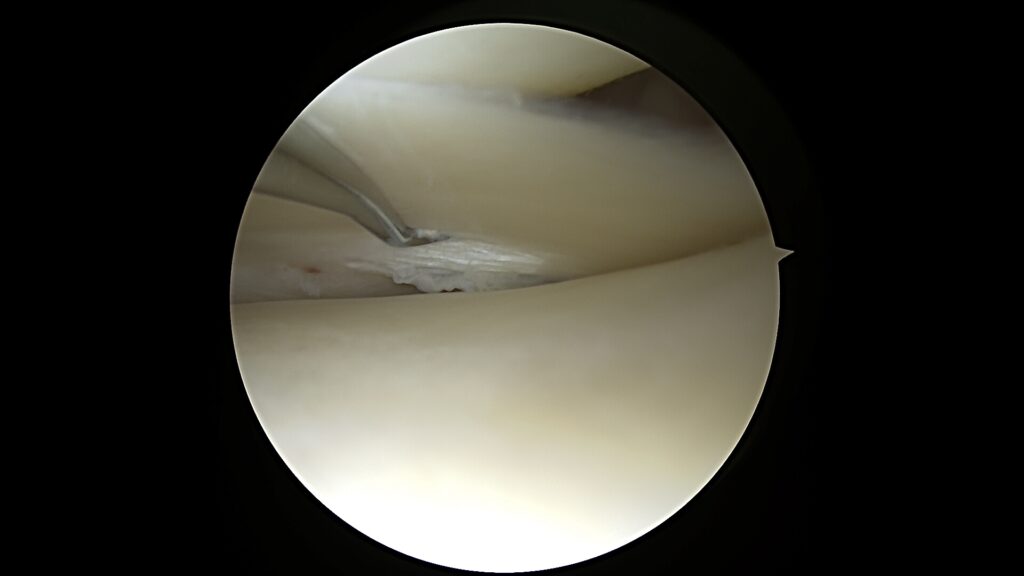

1. Vidinio menisko užpakalinio rago fiksacija (MENIX DUO)

Naudojant MENIX DUO technologiją, vidinio menisko užpakalinis ragas tvirtinamas tiksliai ir saugiai, užtikrinant anatominį stabilumą bei amortizacinę menisko funkciją.